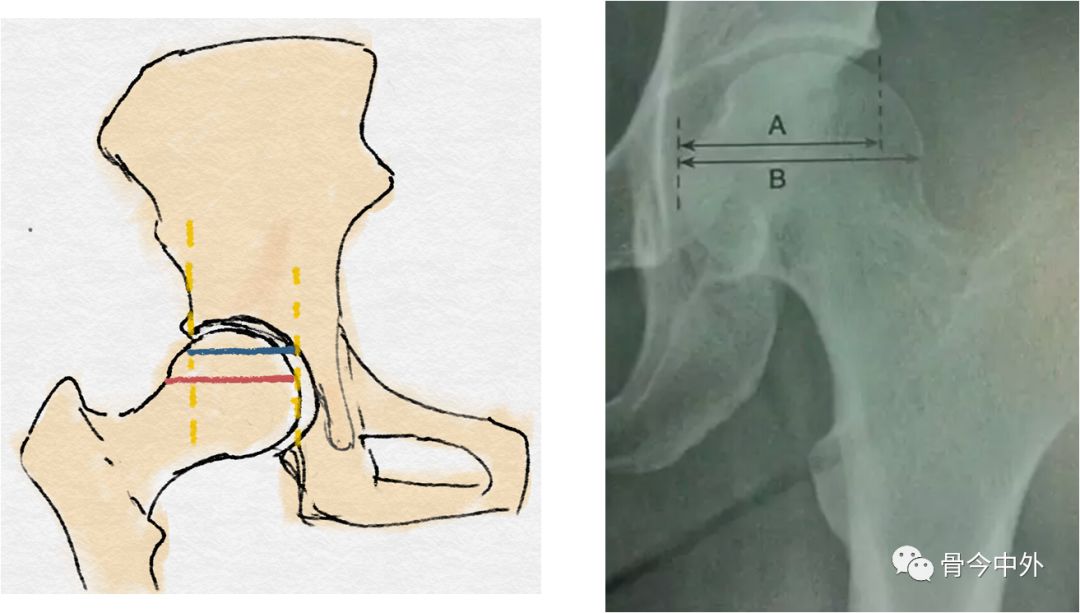

耻骨联合上缘与髋臼外上缘连线(蓝线)

蓝线至髋臼的**距离(红线)(正常:13mm)

髋臼深度:骨盆正位片,耻骨联合上缘与髋臼外上缘连线至髋臼底的**距离,正常时,男13(7~18)mm,女12(9~18)mm,与CE角配合用于评价髋臼发育情况。

股骨头受髋臼覆盖的横径(蓝线)

股骨头横径(红线)(正常:>75%)

股骨头覆盖率(AHI):股骨头受髋臼覆盖部分的横径除以股骨头的横径,正常时应大于0.75。